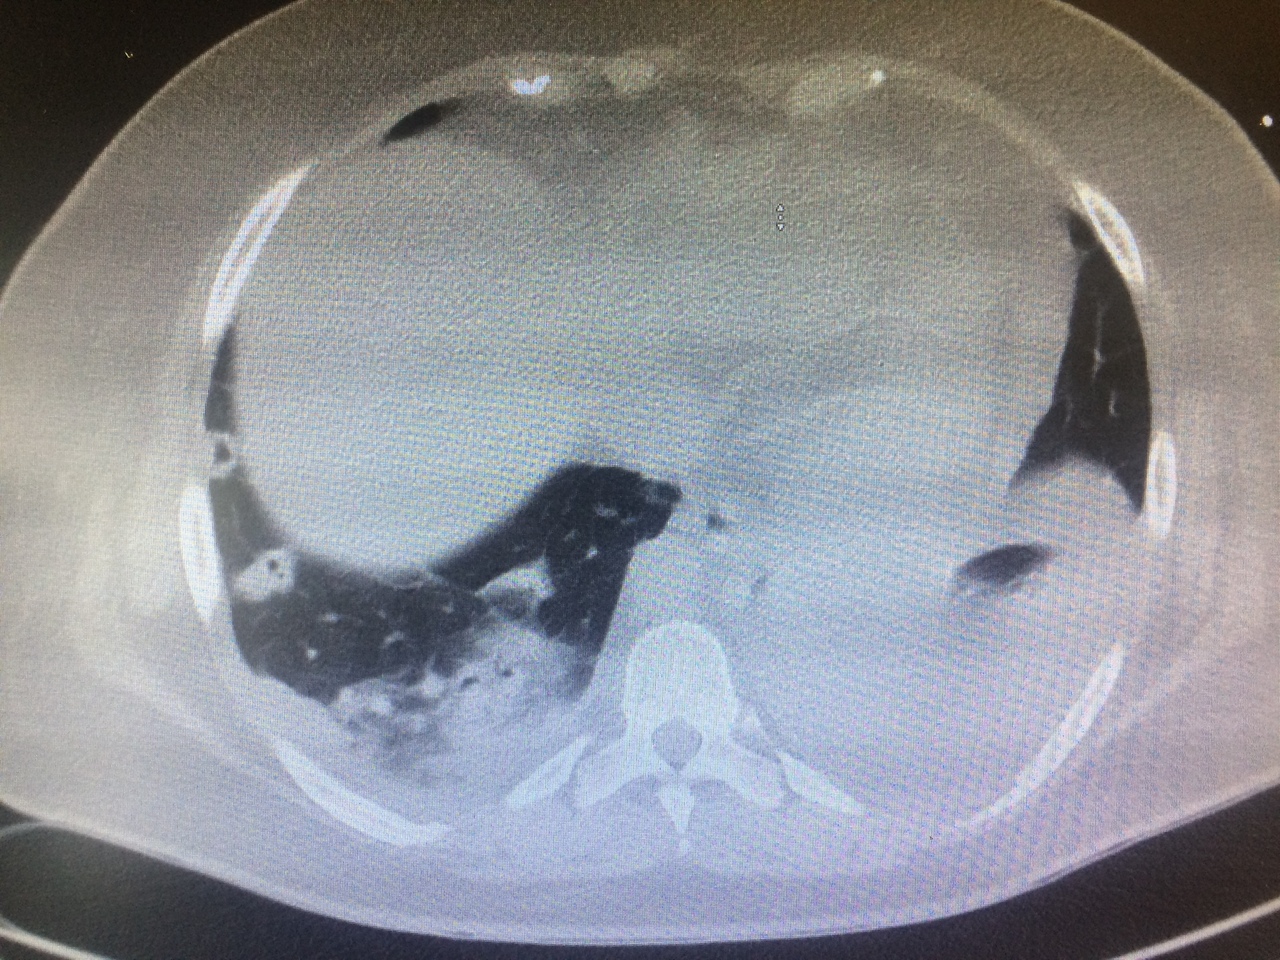

Voici les images du scanner thoracique.

Question 11 : Quelle est votre suspicion diagnostique ?

Syndrome septique chez un porteur de valve prothétique pulmonaire, examen direct suggérant un sepsis à staphylocoques (germe pourvoyeur d’EI), nombreux emboles pulmonaires excavés